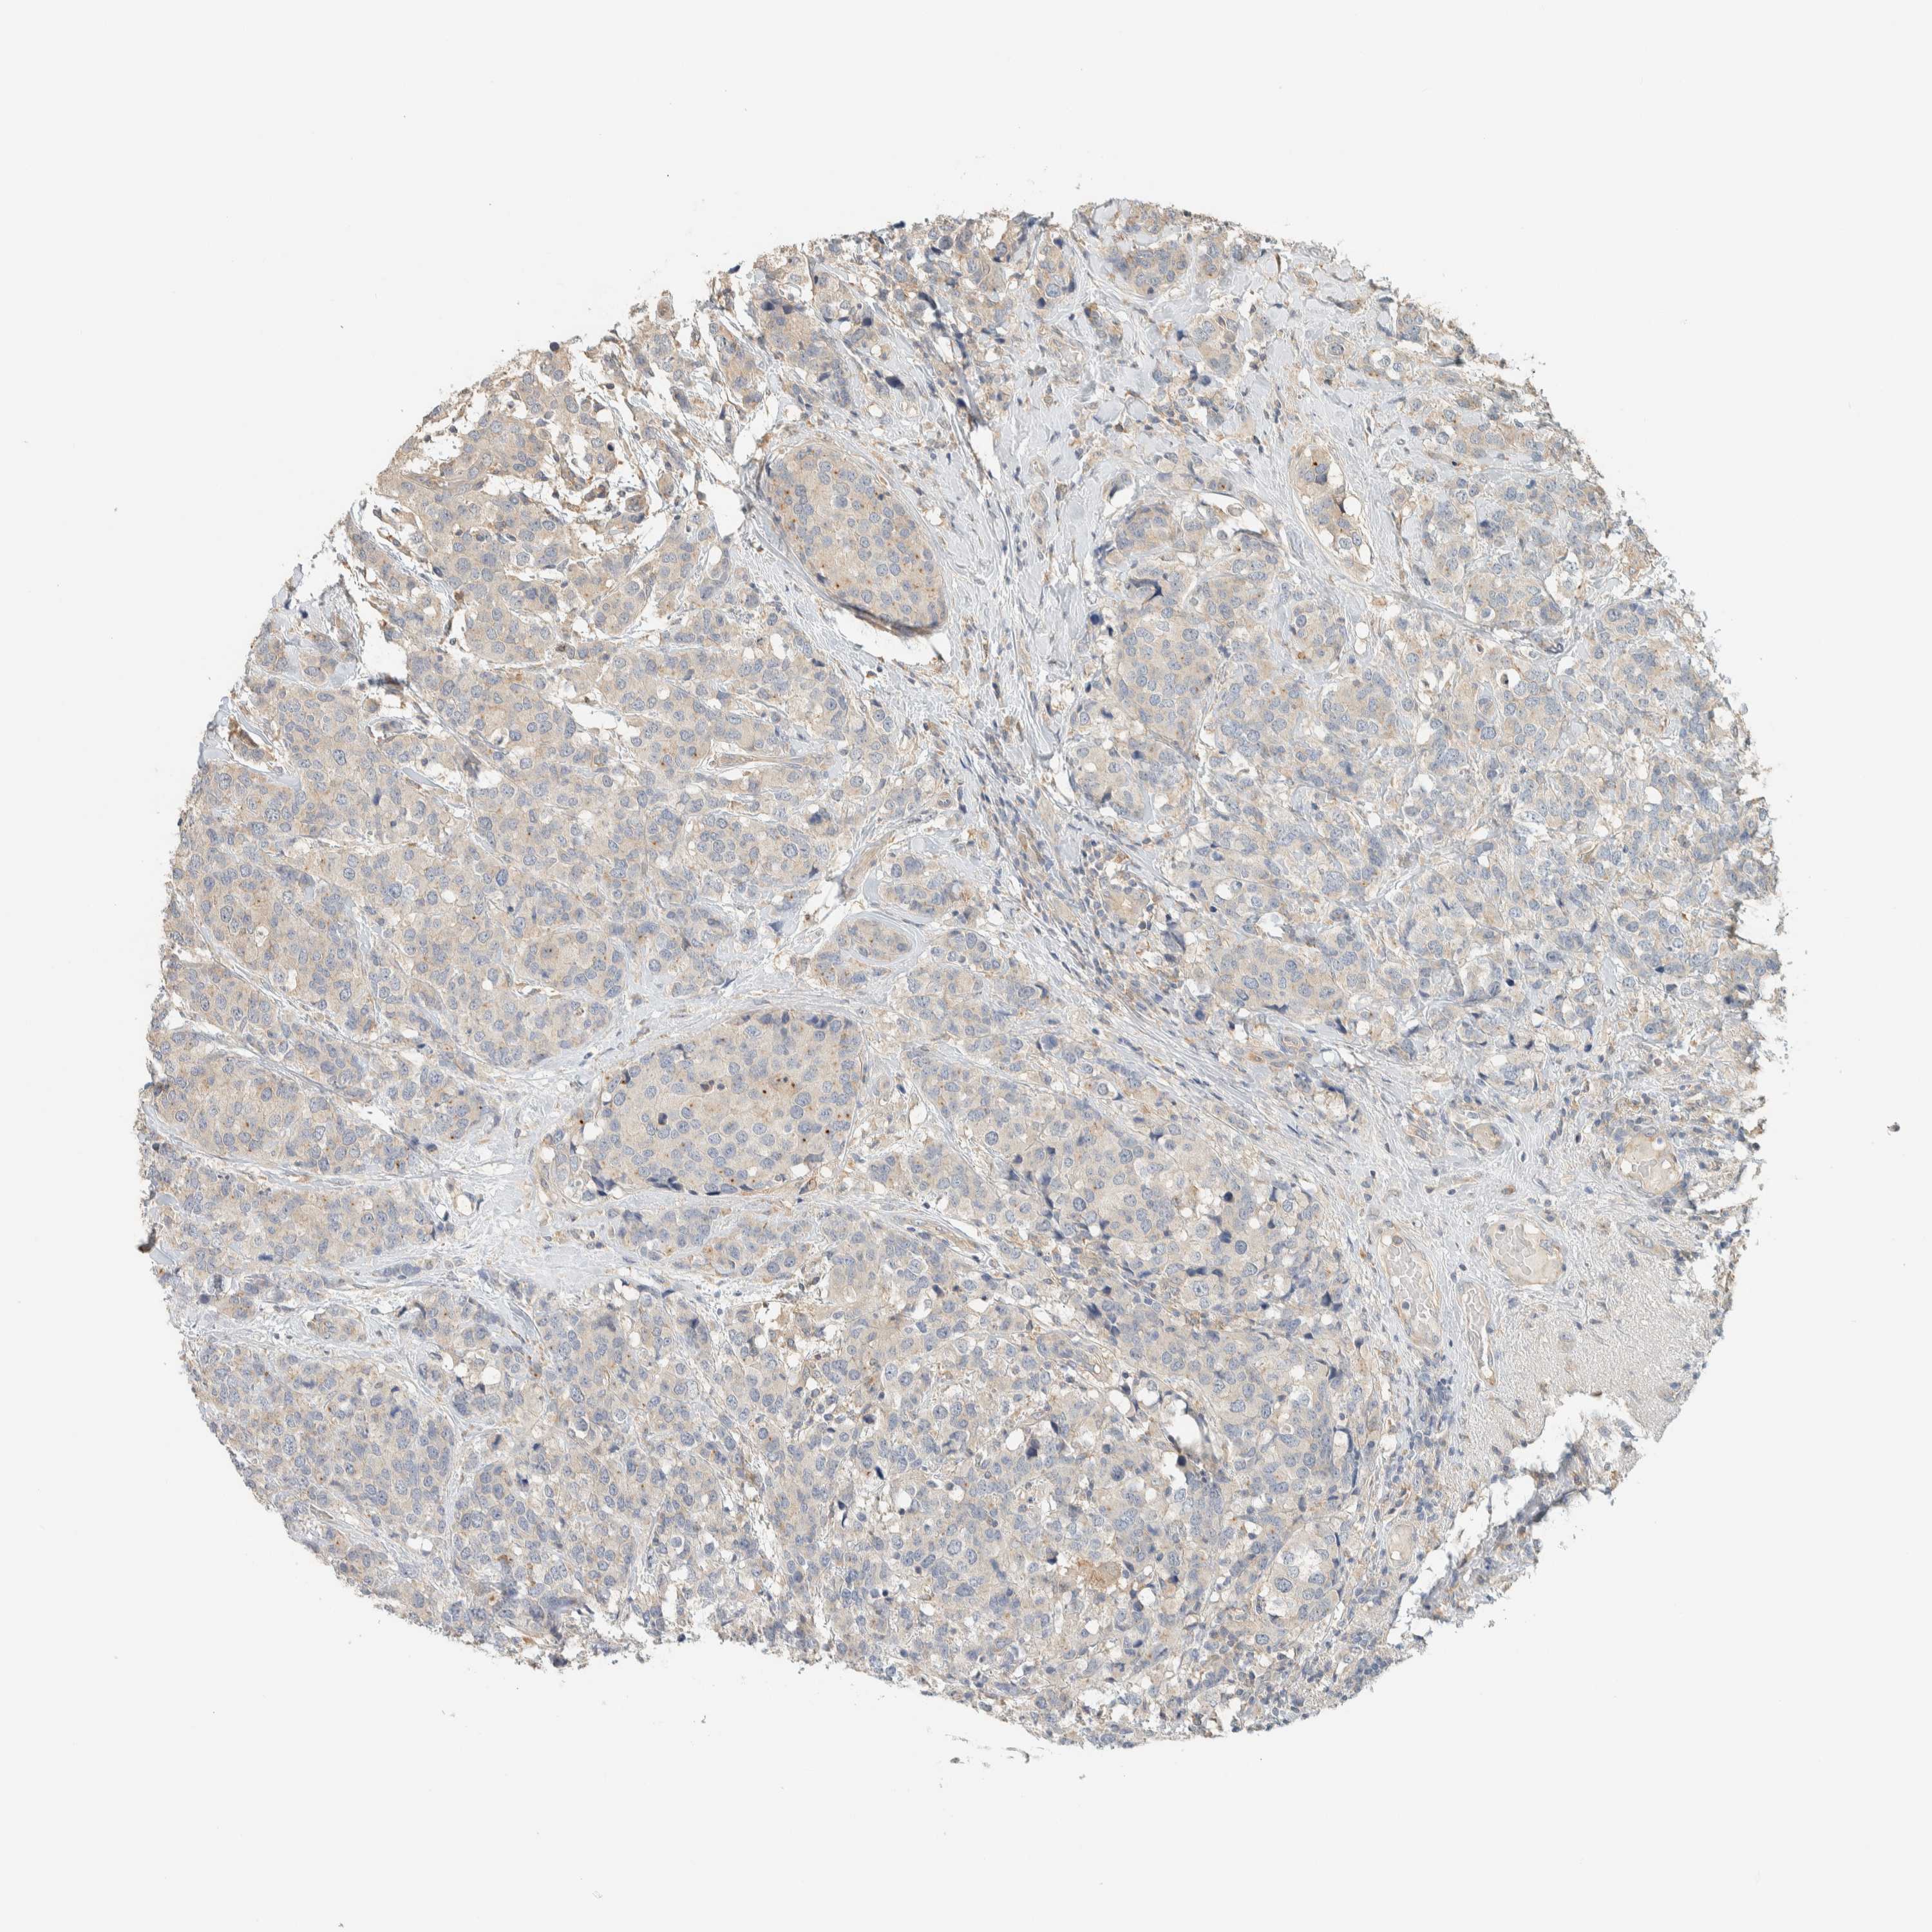

BRCA TCGA BRCA VALIDATION PROTEIN EXPRESSION